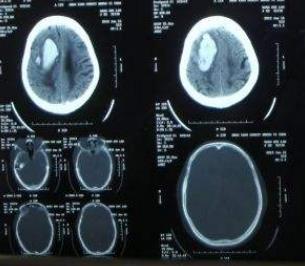

右侧额颞顶叶脑梗死

查体:血压140/80 mm Hg,心率78次/min,呼吸18次/min,嗜睡,双侧瞳孔等大等圆、对光反射灵敏,左侧鼻唇沟浅、口角歪斜,左上肢肌力3+级,左下肢4+级,巴氏征阳性。行头颅CT未见明显异常,MRI提示右侧额颞顶叶及右侧基底结区脑梗死。

诊断:右侧额颞顶叶脑梗死 治疗:予阿司匹林、氯吡格雷片、低分子肝素钠针、依折麦布辛伐他汀片、银杏达莫注射液等药物溶栓、抗血小板聚集、调脂稳定斑块,并给予维生素B1及B2营养神经,他汀类药物降脂及利培酮改善精神症状。治疗4天后患者意识恢复,和家人正常交流,病情稳定出院。